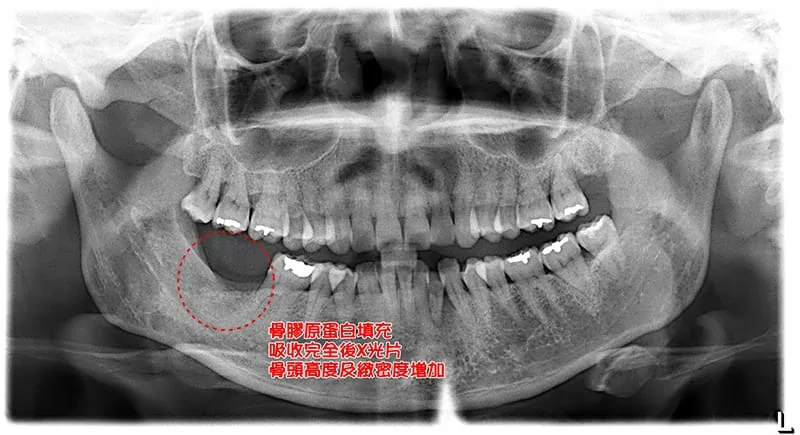

拔牙填補骨膠原蛋白,骨質增生超神奇

局部麻醉下,進行牙齒拔除,並填置骨膠原蛋白後,縫合,等一週牙肉癒合拆線,三個月後,回診檢查骨頭狀況。

( 治療後 )

( 治療後:骨膠原蛋白轉換成正常骨頭,X光片上呈顯骨頭高度及緻密度回升 )